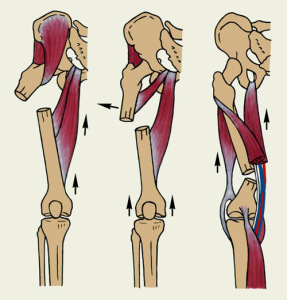

- Диафизарные переломы. Они возникают от непрямого и прямого механизма травмы. Уровень повреждения определяет его вид. Перелом верхней трети бедра из-за действия мышечной тяги приводит к тому, что кпереди смещается центральный отломок. Его смещение также происходит кнаружи. Периферический отломок подтянут кверху. В случае перелома средней трети центральный отломок немного отклонен кнаружи и кпереди, а периферический слегка приведен и смещен кверху. Конечность деформируется из-за сильного смещения и искривления. В случае перелома нижней трети центральный отломок смещается кнутри и кпереди из-за сильных приводящих мышц и тяги сгибателей. Короткий периферический отломок отклонен кзади. Костный фрагмент может повредить нервно-сосудистый пучок.